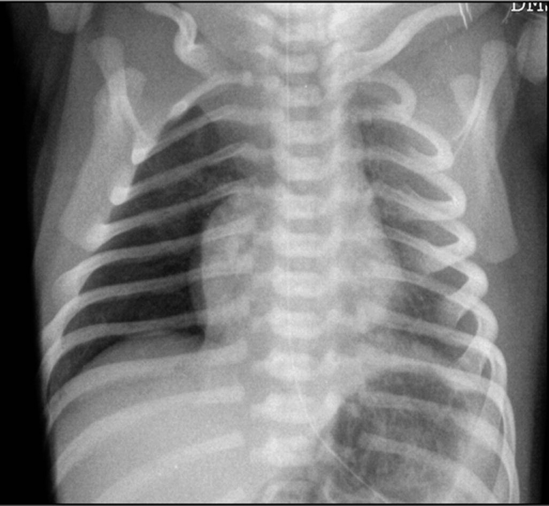

Case 3

A postterm 42 3/7 week gestational age infant is born after induced vaginal delivery. Meconium-stained fluid was noted after rupture of membranes approximately 6 hours before delivery. The infant’s head was delivered easily; however, the infant’s body was delivered 4 minutes after the delivery of the head, causing shoulder dystocia. The infant at 5 minutes was cyanosed, had a weak cry, mild flexion of the limbs, no spontaneous movements, with a heart rate of 160.

What do you expect the cause of respiratory distress to be?

- Meconium aspiration syndrome

Xray findings

- Hyperinflation,

- Consolidation,

- Patchy infiltrates

- If severe, air leak and pneumomediastinum may occur

- Lines going from inside to outside

The infant has been on a ventilator for about 6 hours when you are called to the bedside for sudden decompensation with decreased saturations as low as 30%, bradycardia, and absent breath sounds on the right.

- What do you expect happened? pneumothorax

- What is your immediate action? right needle decompression 2nd intercostal mid clavical

well demarcated right lung pnumothorax - pushed

effusion pulls

Deep Sulcus Line

- Notice:

“Deep sulcus line” indicating pneumothorax.